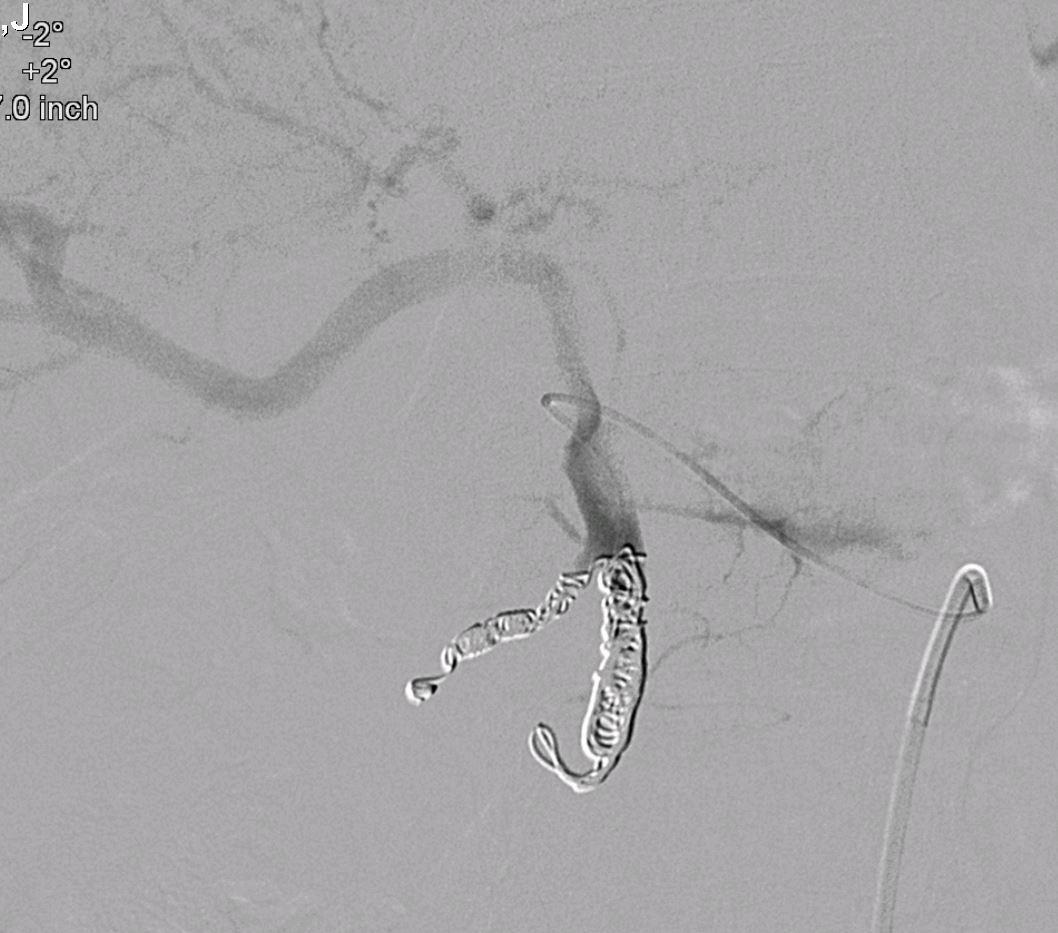

外伤后出血的栓塞

外伤后可见造影剂外溢 |

微导管选择至出血血管 |

出血血管的微弹簧栓子栓塞 |

栓塞后造影 |